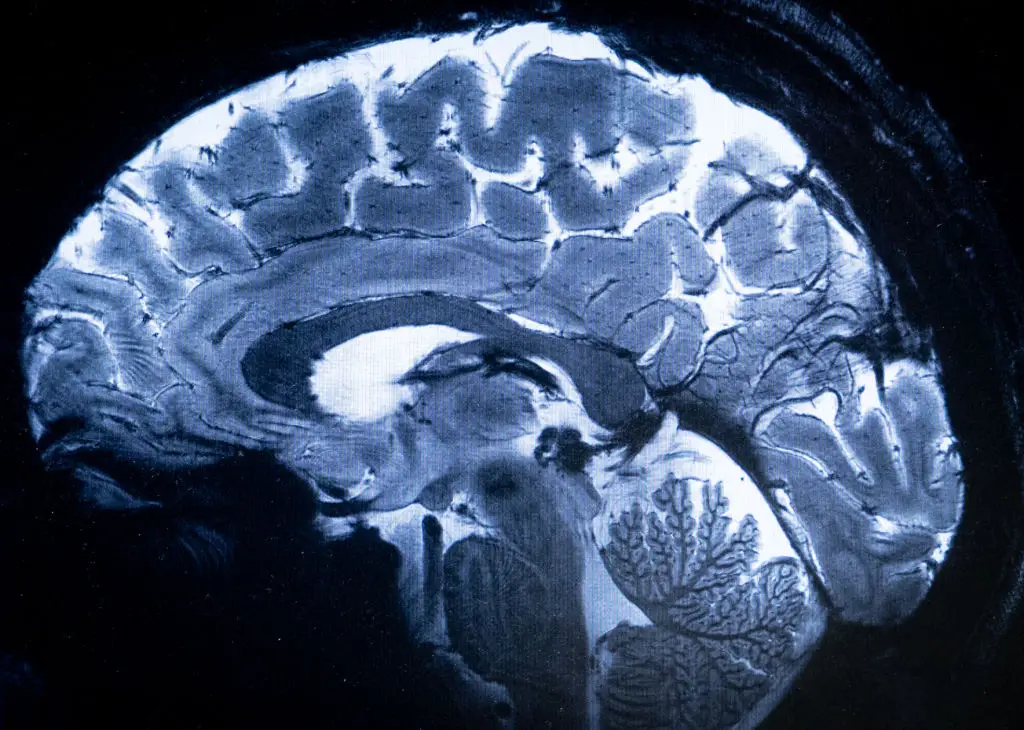

However, it's less shocking when you factor in that the idea that a brain's frontal and prefrontal cortex - which is responsible for our impulse control and emotional regulation - doesn't finish developing until the age of 25, which is a perfect excuse to write off any embarrassing actions during the early years of adulthood.

Well, according to Mindea, this is because our brains go through a period of 'pruning' once we progress into adolescence, with unused neural connections from our childhoods going into 'atrophy'.

Things don't get much better once we pass our peak either, with Mindea adding that the brain 'gradually atrophies or shrinks' once we pass the age of 65.

Put simply, this means we can look forward to a decline in our problem solving and processing abilities.